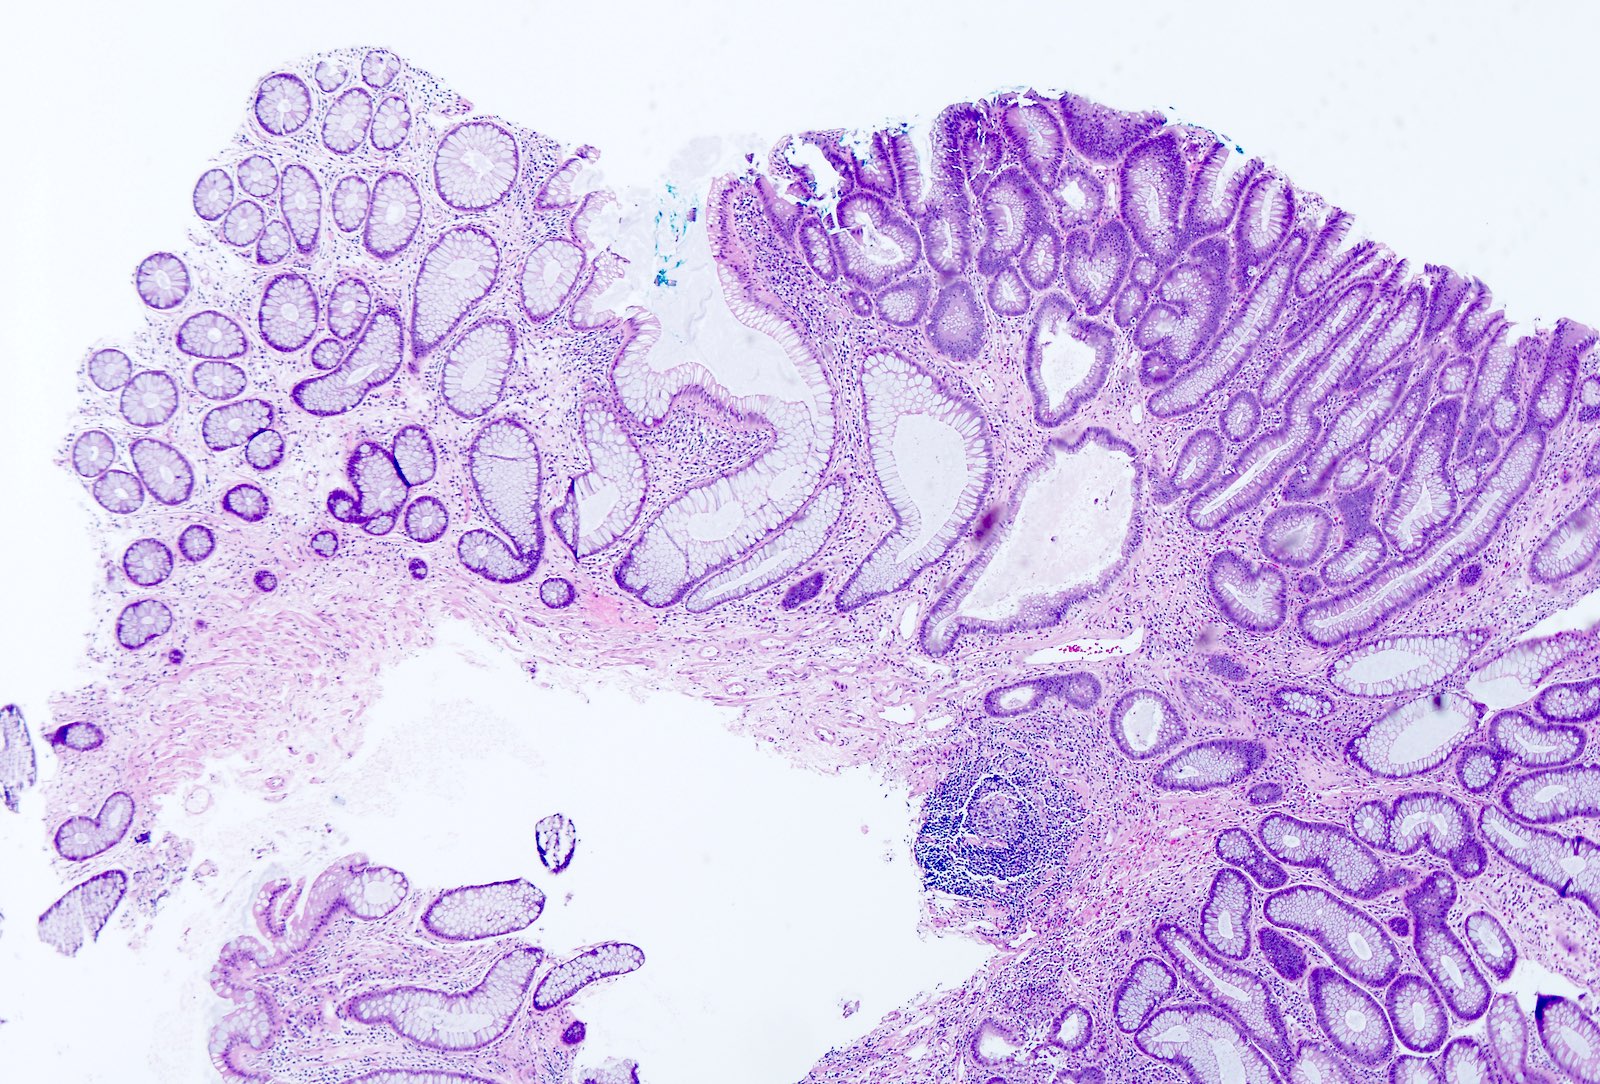

Microscopic (histologic) description

- Polypoid colonic mucosa covered with dysplastic epithelium comprised of hyperchromatic, elongated nuclei arranged in a pseudostratified manner

- Dysplasia is typically low grade but may also be high grade, with architectural (cribriforming, luminal necrosis) and cytologic changes (vesicular chromatin, nucleoli, loss of basal polarity)

- Abrupt transition from normal to dysplastic mucosa is commonly present

- Variable amounts of mucin loss

- Metaplasia may be present: osseous, squamous or Paneth cells (J Clin Pathol 2005;58:220, J Surg Oncol 1984;26:130)

- Pseudoinvasion can mimic progression to adenocarcinoma but displaced glands are benign and surrounded by lamina propria and often hemosiderin (Mod Pathol 2015;28:S88)

- May rarely show clear cell features (Am J Surg Pathol 2010;34:1344)

Microscopic (histologic) images

Contributed by Andrew L.J. Dunn, M.D. and Christopher Hartley, M.D.

Contributed by @Andrew_Fltv and @liverwei on Twitter